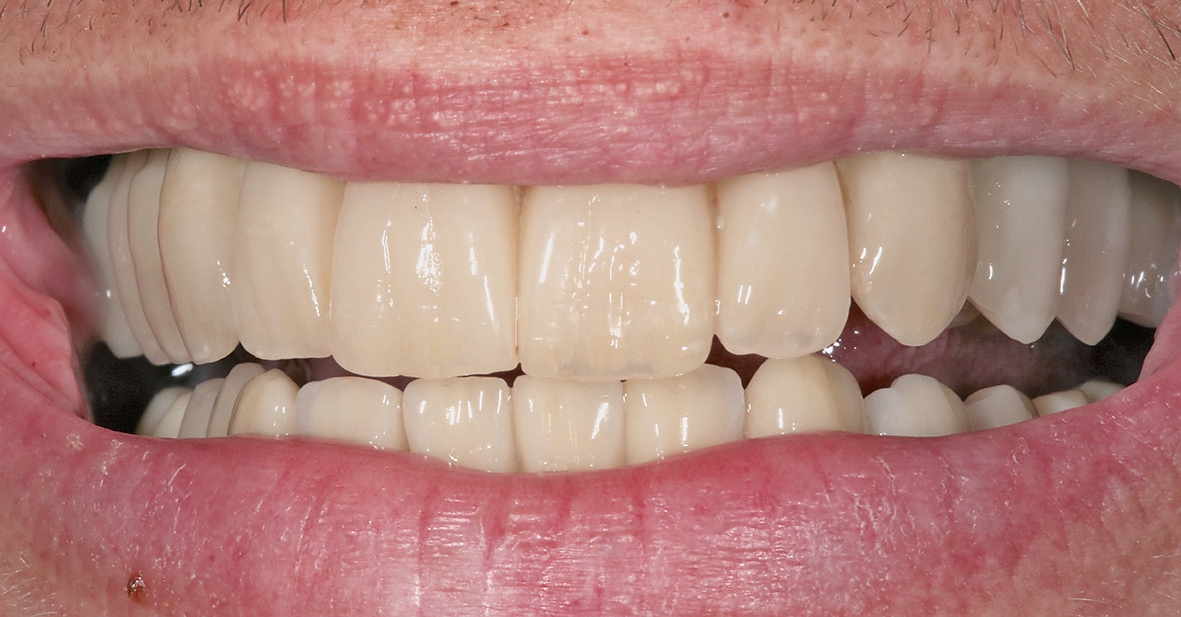

Bei reizlosem postoperativem Verlauf konnten die Implantate wie geplant nach drei Monaten freigelegt werden. Um das Emergenzprofil für die Prothetik möglichst optimal zu gestalten, kamen dabei sowohl zylindrische als auch wide body Gingivaformer zum Einsatz. Nach einer Heilungszeit von zwei Wochen für das Weichgewebe wurde der Patient für die prothetische Phase an die zuweisende Zahnarztpraxis (Dr. Andreas Karg, Lenggries) zurücküberwiesen. Dort wurde der Unterkiefer mit drei Brückensegmenten 46-44, 43-33, 34-46 definitiv versorgt. Zunächst erfolgte nochmals eine exakte zentrische Relationsbestimmung mit auf den Implantaten verschraubten Gerber-Stützstiftregistrat-Platten (Abb. 16). Anschließend wurden die Brückengerüste in CAD/CAM-Technik konstruiert und aus Zirkonoxid gefräst und individuell keramisch vollverblendet. Im Oberkiefer wurde zunächst ein auf provisorischen Abutments reversibel zementiertes Langzeitprovisorium aus PMMA mit glasfaserverstärkten Strängen (Targis Vectris) eingegliedert, um Phonetik, Ästhetik, Hygienefähigkeit und die Bisslage nochmals über eine Tragezeit von sechs bis neun Monaten zu evaluieren und falls notwendig letzte Korrekturen durchführen zu können (Abb.17-23). Danach ist die definitive Versorgung mit vier einzelnen Brückensegmenten in regio 16- 14, 13-11, 21-23 sowie 24-26 geplant.

Das implantatprothetische Konzept mit acht Oberkieferund sechs Unterkieferimplantaten wurde gewählt, um große Brückenspannen zu vermeiden. Durch die Implantatposition sind im Oberkiefer vier und im Unterkiefer drei jeweils kurzspannige Brücken realisierbar (16-14, 13-11, 21-23, 24-26, 36-34, 33-43, 44-46). Dies bringt Vorzüge hinsichtlich der Zahnersatz-Passung einerseits, erhöht aber auch die Reparaturfreundlichkeit im Falle eines Chippings o.ä. signifikant.

Bei Implantatversorgungen in beiden Kiefern ist das Problem von Chipping durch die fehlende physiologische Zahnbeweglichkeit einerseits, aber auch den fehlenden „occlusal sense“ andererseits eine große prothetische Herausforderung. Daher eignen sich hierfür entweder monolithische Konstruktionen oder die Verwendung von hochverdichtetem Komposit als Verblendungsmaterial in einem Kiefer. Bei monolithischen Restaurationen, z. B. aus Zirkonoxid, ist zwar das Chipping-Risiko ebenfalls minimiert, andererseits sind die hierbei entstehenden unphysiologisch hohen okklusalen Kräfte kritisch zu bewerten. Bei Patienten, bei denen funktionelle Parameter wie Bisslage und -höhe verändert wurden bzw. die von herausnehmbaren auf festsitzenden Zahnersatz umgestellt werden, ist darüber hinaus die Verwendung von Langzeitprovisorien sehr empfehlenswert, um evtl. noch erforderliche Feinanpassungen zu ermöglichen.